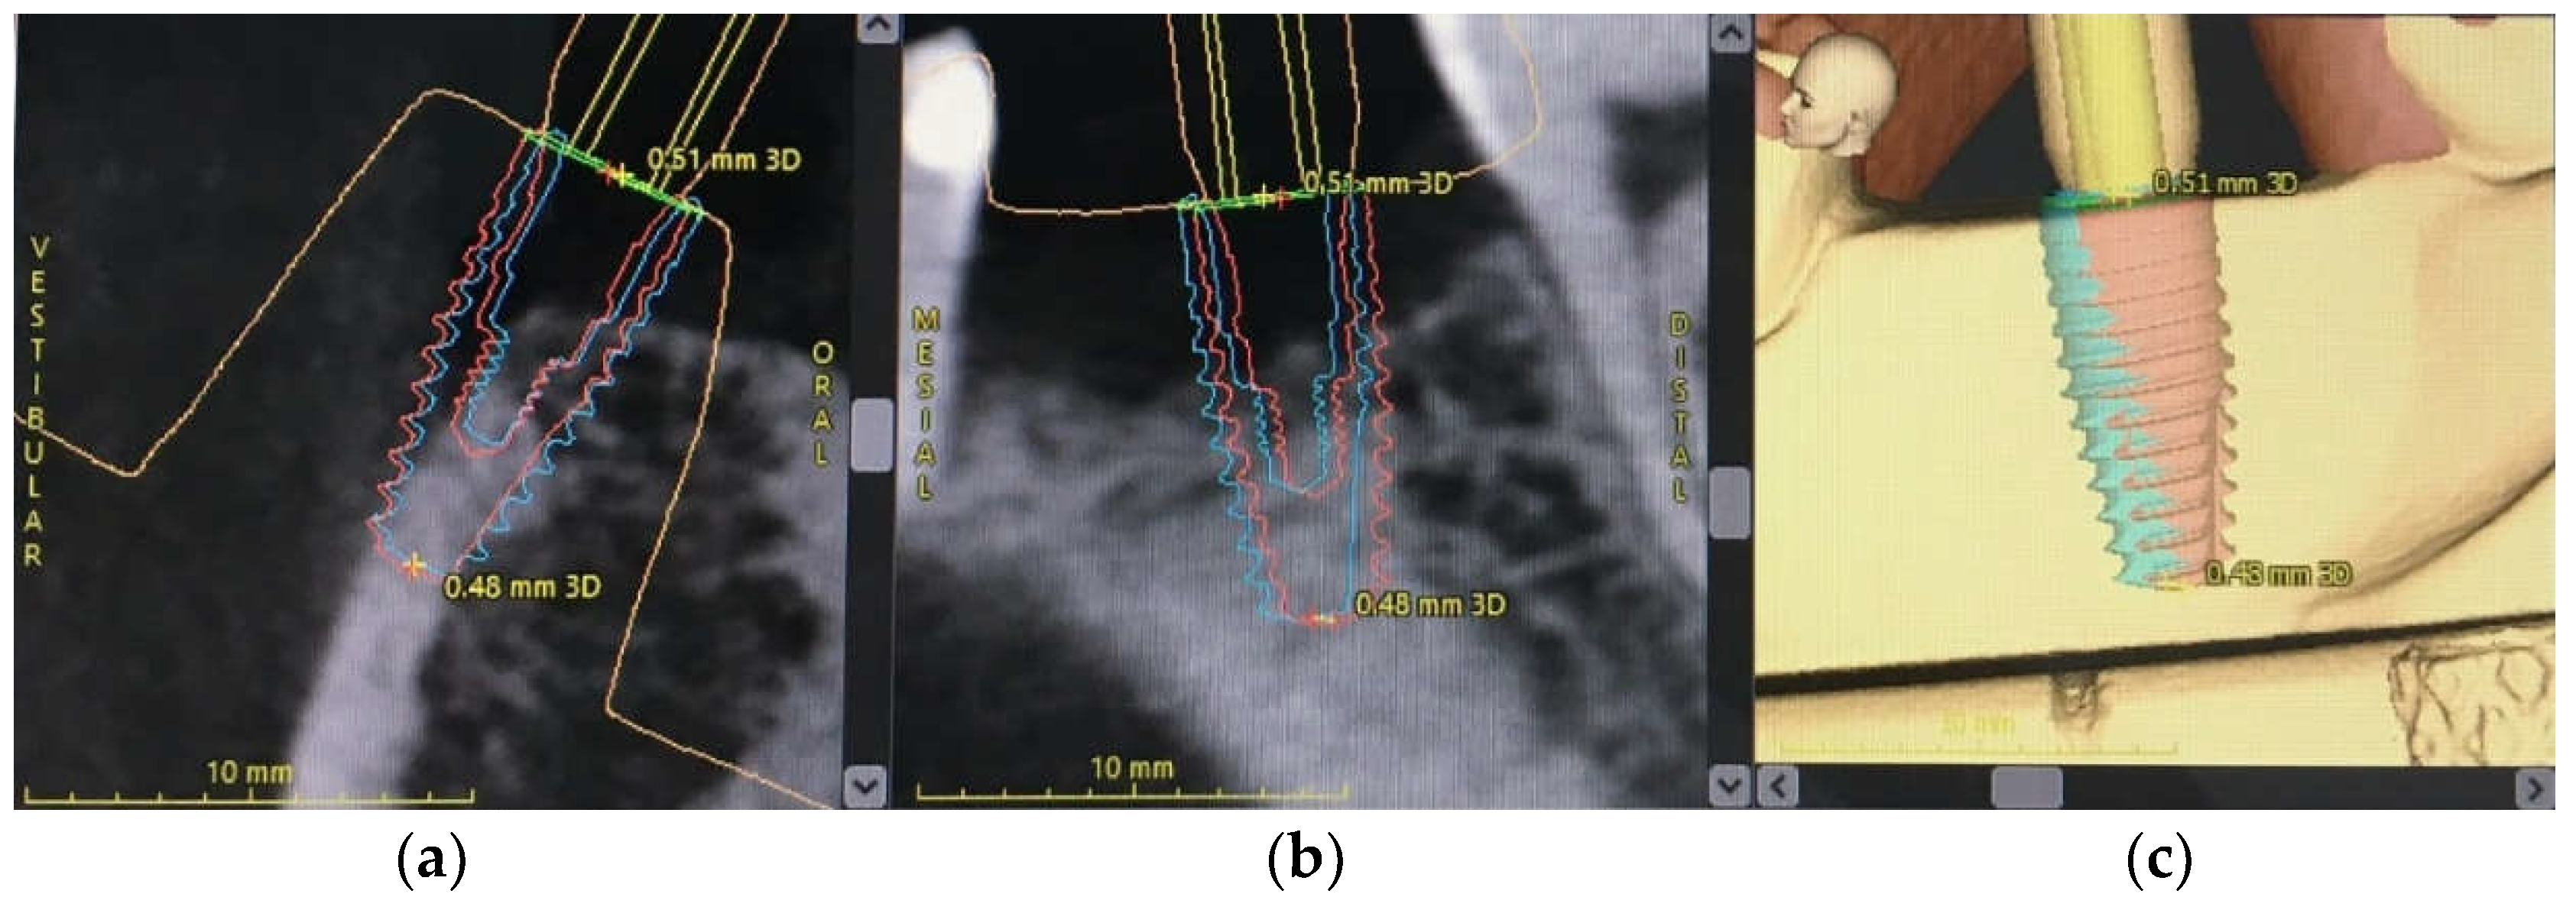

2.5. Implant Position Accuracy Measurement

- Linear deviation from the implant platform: the linear displacement in mm between the planned and placed implants, measured at the center of the implant platform.

- Linear deviation from the implant apex: the linear displacement in mm between the planned and placed implants as measured at the center of the implant apex.

- Linear deviation of the implant depth: the depth deviation in mm between the planned and placed implants.

- Deviation of the implant axis or an angular deviation: the deviation in degrees (°) between the center axis line of the planned and placed implants.